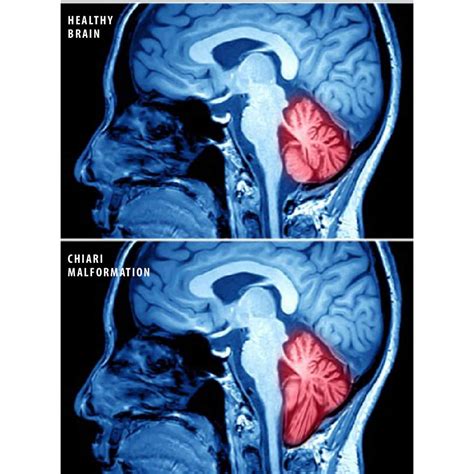

Understanding the complexities of the human brain requires an awareness of conditions that can affect the structural integrity of the central nervous system. Among these, Chiari malformation is a condition that occurs when brain tissue extends into the spinal canal. This happens when the skull is smaller than normal or misshapen, pressing on the brain and forcing it downward. Identifying Chiari Malformation Symptoms early is essential for effective management and long-term health, as these indicators can vary significantly from person to person depending on the severity of the downward displacement.

Chiari malformation is classified into different types, ranging from Type I to Type IV, based on the anatomy of the brain tissue displacement and the severity of the condition. In many cases, the condition is congenital, meaning it is present at birth, but symptoms may not manifest until late childhood or adulthood. The structural abnormality creates pressure on the cerebellum and the brainstem, which can impede the flow of cerebrospinal fluid (CSF). When this flow is disrupted, it can lead to a variety of neurological issues.

Because Chiari Malformation Symptoms are often nonspecific, medical professionals rely heavily on diagnostic imaging to confirm the diagnosis. Magnetic Resonance Imaging (MRI) is the gold standard for visualizing the brain and the spinal canal. An MRI can clearly show the position of the cerebellar tonsils relative to the foramen magnum—the opening at the base of the skull.

In some instances, specialized MRI sequences, such as Cine MRI, may be used to observe the pulsatile flow of cerebrospinal fluid. This helps clinicians determine if there is a blockage or obstruction that requires surgical intervention, such as a posterior fossa decompression, to create more space for the cerebellum and restore normal fluid circulation.